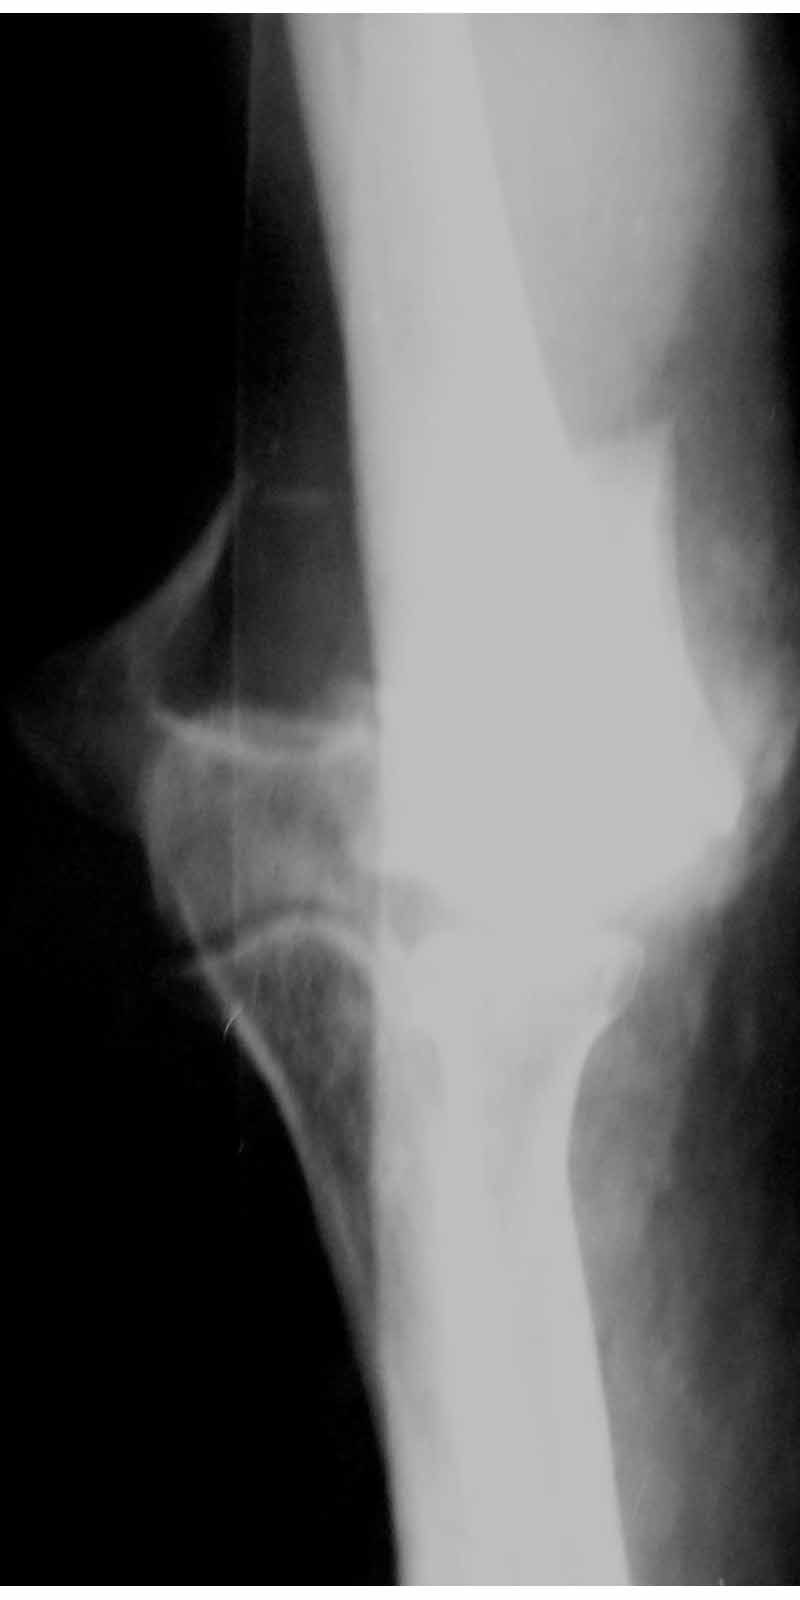

Солидарен с мнением обоих Александров (Челнокова и Рыкова): точную репозицию такого перелома вряд ли удастся выполнить закрыто. Даже во время открытого вмешательства это сделать непросто. Неслучайно предложен костно-пластический доступ с временным отсечением локтевого отростка. И по методу фиксации согласен с Александром Челноковым: 2 пластины. В качестве примера привожу рентгенограммы одного из наших пациентов с аналогичным повреждением.

С уважением, А. Золотов, Приморский край.